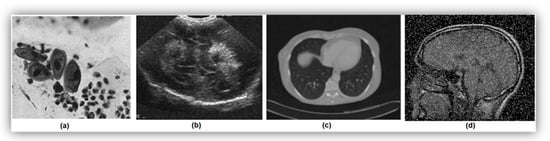

Noise in images can arise from various sources, resulting in random distortions such as color imbalances or brightness issues. In the context of Pap smear images, the presence of noise can significantly impact the accuracy and reliability of differentiating between nuclear and non-nuclear features, leading to potential misclassifications and decreased performance in cytoplasm and nucleus segmentation. Examples of different types of noise are shown in Figure 3 [17,18,19,20]. Biomedical images commonly exhibit different types of noise, including Poisson noise, speckle noise, Gaussian noise, and impulse noise.

Poisson Noise: Poisson noise occurs when there are an insufficient number of energy-carrying particles, such as electrons or photons, in an electronic or photosensitive device. Factors contributing to Poisson noise can include low levels of radiation, inefficient detectors, or high background radiation.

Speckle Noise: Speckle noise is a granular and multiplicative noise that degrades image quality by reducing resolution, contrast, and pixel information. It is caused by the constructive and destructive interference of coherent waves interacting with a rough or textured surface or interface. In medical imaging, such as ultrasound, speckle noise is a result of the interaction of ultrasound waves with small structures or tissue interfaces that have different acoustic impedance values.

Gaussian Noise: Gaussian noise, also known as random or white noise, is additive in nature and follows a normal distribution. It arises from random variations in pixel intensities due to factors such as electronic noise in the imaging system, photon noise during acquisition, or natural tissue variation.

Impulse Noise: Impulse noise, also known as salt and pepper noise, manifests as isolated bright or dark pixels or bursts of random noise in medical images. It can obscure important details or create false features, making image interpretation challenging. Impulse noise arises from random spikes or drops in pixel intensity values, often due to sensors malfunctioning.

Figure 3. Samples of various noise types in medical images: (a) Poisson noise, (b) speckle noise, (c) Gaussian noise, and (d) impulse noise.